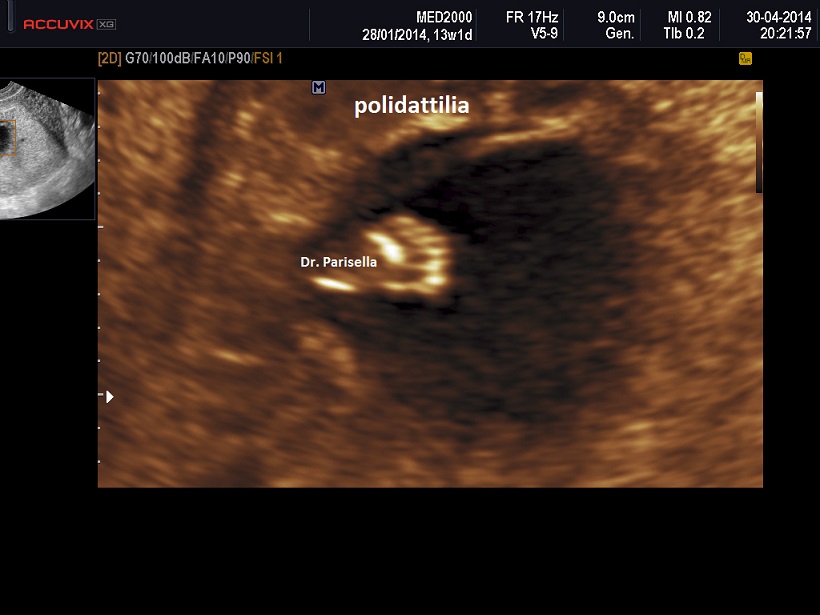

La MICROMELIA SEVERA e l’ IPOPLASIA TORACICA SEVERA (legata al torace stretto con coste corte) sono i segni principali presenti in tutte e quattro i tipi di SRPS e che indirizzano verso una corretta diagnosi. La POLIDATTILIA è presente nei primi due tipi, meno frequentemente nel tipo III, è assente nel tipo IV.

La MICROMELIA SEVERA e l’ IPOPLASIA TORACICA SEVERA (legata al torace stretto con coste corte) sono i segni principali che indirizzano verso una corretta diagnosi. La POLIDATTILIA, sempre presente, è di tipo postassiale ed interessa sia mani che piedi. Spesso è presente idrope.